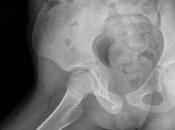

COXA VALGA BILATERAL

El 26 diciembre 2024 por Godieboy :